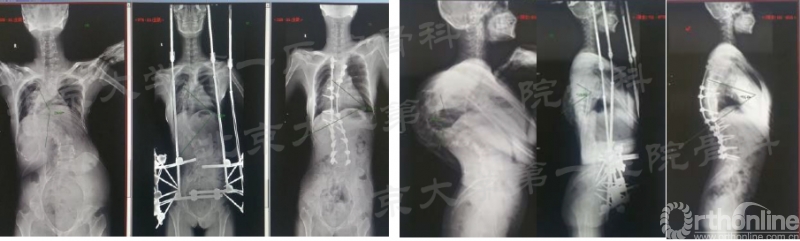

典型病例1

21岁女性,早发型脊柱侧后凸畸形伴限制性通气功能障碍。15年前出现脊柱侧弯,之后进行性加重, 运动耐量欠佳,跑步后胸闷明显,无神经症状。牵引2周后身高增加14cm,牵引第3周时出现右下肢力弱,及时放松牵引后肌力恢复。 牵引后冠状面矫形率为41.4%,矫形术后冠状面总矫形率60.0% 。牵引后矢状面矫形率为55.5%,矫形术后冠状面总矫形率66.4%。